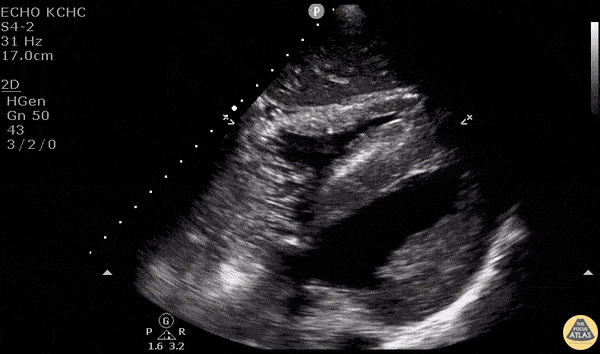

A central venous catheter was placed in the right internal jugular under ultrasound guidance and sub-xiphoid view was obtained. Saline was rapidly flushed through the brown port and turbulent saline can be seen traveling through the right side of the heart. - Dr. Matthew Riscinti and Dr. Isaac Gordon - Kings County Emergency Medicine